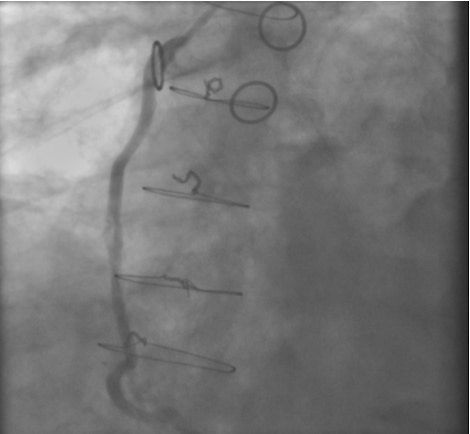

The most commonly used catheters for left heart catheterization and vein graft angiography can be seen in Figure 1 and Figure 4-13. Most of the vein grafts have horizontal take off and can be successfully engaged using a commonly used Judkins right number 4 (JR4) catheter. The JR4 catheter is the most commonly used catheter for the engagement of the right coronary ostium with horizontal take off. However, many vein grafts have unusual take off requiring different catheters. Many right coronary vein grafts have steep inferior take off making the ostial engagement with JR4 difficult or impossible (Figure 10). In such a scenario, a multipurpose catheter which has a shallow angulation is the best choice (Figure 11). The second major challenge in engaging vein graft ostia, particularly vein grafts supplying the left coronary arteries, is the shape of the aorta. A large aorta can make it very difficult for the JR4 catheter to reach the ostial vein grafts. In such a situation, Amplatz (AR) right and left (AL) catheters can be very helpful to reach the vein graft ostia. Amplatz catheters have a larger primary curve and have been used successfully in unusual superior take off of left coronary arteries or vein grafts and in large aorta. Amplatz catheters are available in different sizes (from smaller to larger curve: AR 1, AR2, AL2, AL2 and AL3). Occasionally, a very superior take off of a vein graft requires specially designed bypass graft catheters. Amplatz catheters are also extremely helpful in engaging native right coronary ostium with anterior take off.

PCI of the vein and arterial grafts have unique challenges. For any PCI, guide support is very important for successful balloon and stent delivery. In a tortuous vein graft with a steep angle, advancement of a stent can be very difficult and challenging. Therefore, it is important to choose the best available catheter before starting PCI. Similar to the right coronary angiography, a JR4 guide catheter is most commonly used in this setting. However, Amplatz guide catheters for left vein grafts and multipurpose catheters for right vein grafts are better choices in certain anatomy. In Figure 8 and Figure 10 two examples of poor guide support in two vein graft interventions can be seen. Initially, a JR4 guide was used for PCI of the vein graft supplying the left anterior descending artery (LAD) without any success. However, after changing the guide to an Amplatz left 2 guide catheter, we achieved excellent support without any difficulty in advancing two stents (Figure 9). In Figure 10, difficulty is illustrated in engaging the vein graft ostium supplying the right coronary artery with a JR4 catheter. This vein graft has a very steep inferior take off from the aorta. After changing the guide to a multipurpose catheter, we were able to deliver three stents successfully without any difficulties (Figure 11). Similar challenges exist in the treatment of the left IMA or right IMA. These arterial grafts can be extremely tortuous making stent delivery very difficult. It may be necessary to use short length stents for a better deliverability or stents with lowest profile. Usually, similar to the native coronary intervention, a 6 French guide is appropriate for the routine use.